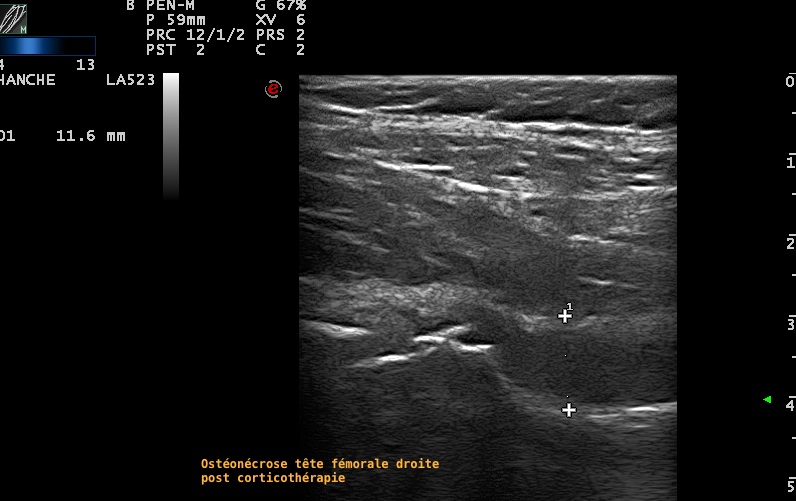

Aspect échographique d'une ostéonecrose aseptique de la tête fémoral avec épanchement associé, chez une jeune fille, dans un contexte de corticothérapie dans le cadre d'une hémopathie